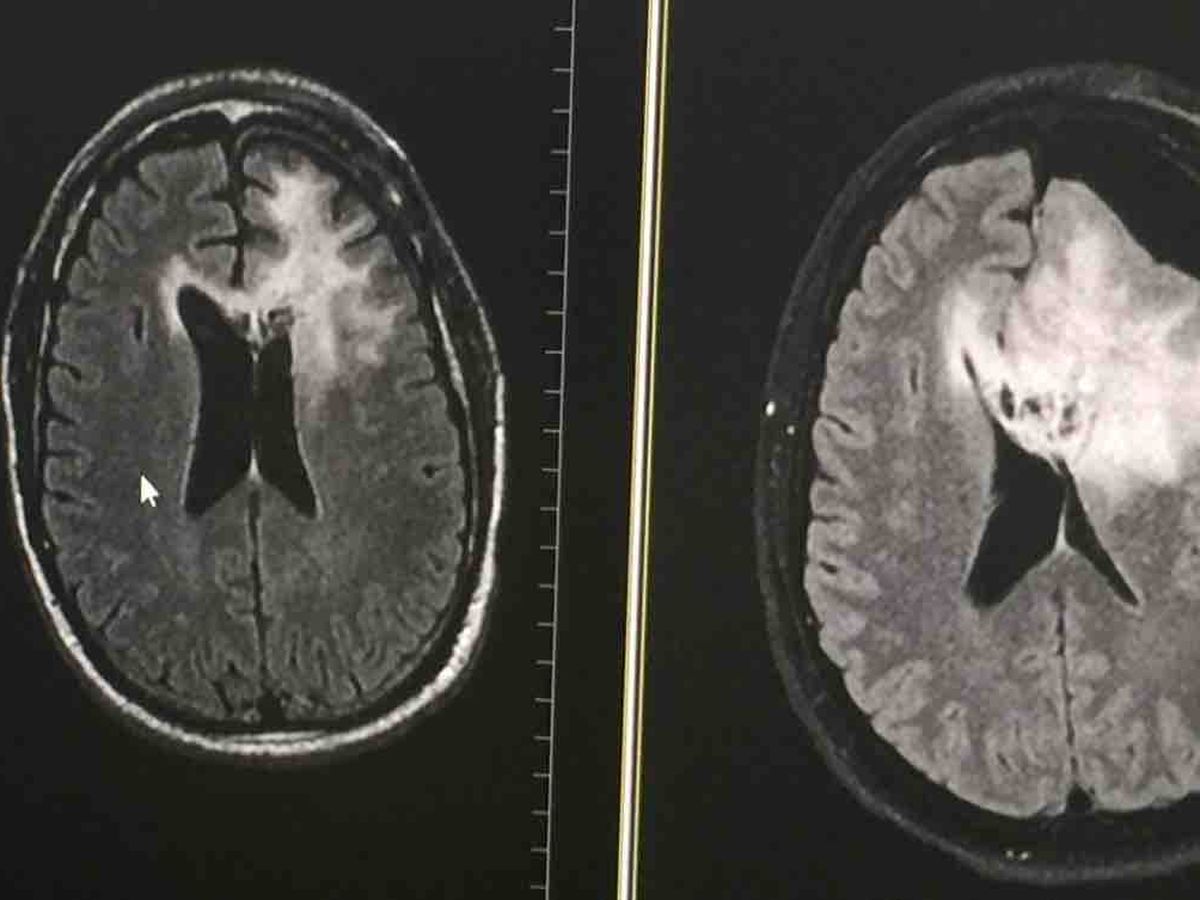

A word of advice......Live today like it is your last day on earth. Hearing the Doctor tell you that you have a Brain Tumor is bad news no matter how you try and spin it. Having the pathology report come back to tell you that the type of Brain Tumor you have is Glioblastoma-GBM is even worse news. Finding out that no one has lived from this tumor ruins the best of days. I am an eternally optimistic person. Always the life of the party. Always happy. But knowing I probably will not make it to the end of the year can definitely make for a sad and bad day. I have a lot to be thankful for. All my friends that have reached out and outpouring of “well wishes” and prayers that I have received have been emotionally overwhelming. I can never attempt to put into words how much my heart is bathed in the love and appreciation of feeling the awesome joy I feel from you. I truly appreciate the love.

I have been asked by a lot of you. “Is there anything I can do to help?”. The only thing I want for the rest of my life is to make sure my 13 year old daughter is taken care of. I am so grateful that the world’s top Neurosurgeon at UCLA was able to do my surgery. I have to admit it was kind of trippy them waking me up during Brain Surgery to talk to me and ask me questions. It was explained to me later that this was so they did not cut the wrong part of my brain out. I was so impressed by my treatment at UCLA, that my daughter now wants to go there. This is kind of a big deal because I went to USC. If I had a wish it would be to live to see her attend UCLA. I will remain positive and pray.

Since my surgery I have accepted into a clinical trial called www.MoonShot2020.org Even though my type of brain tumor KILLS EVERYONE! I have hope that I will be the 1 person who lives.